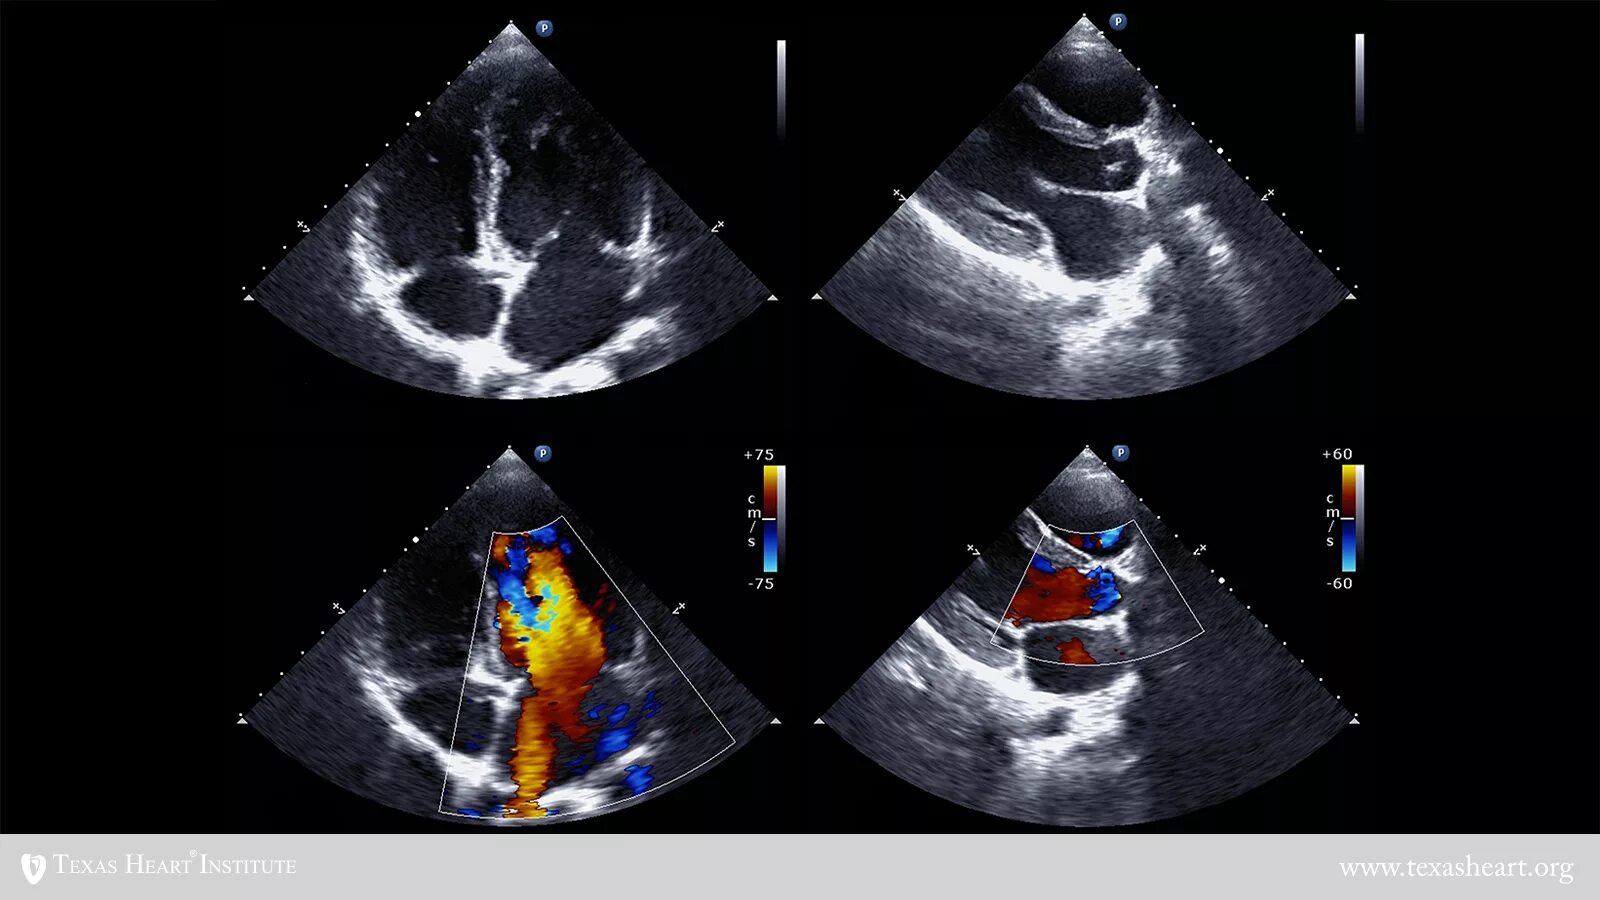

Узи сердца показывает сердечную недостаточность